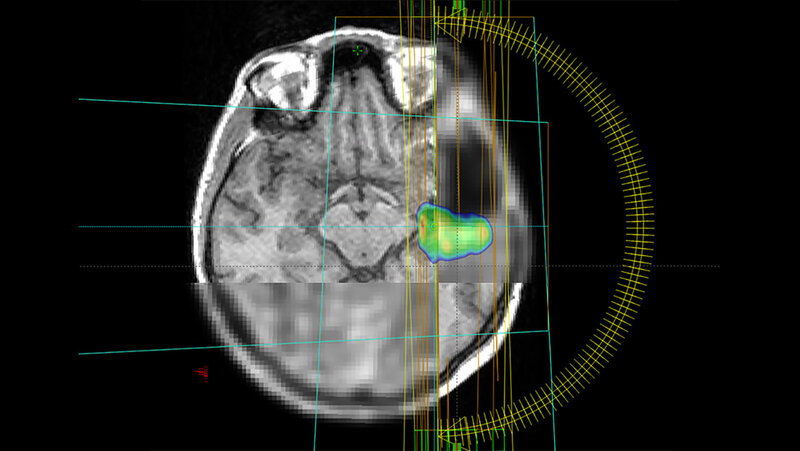

Statt wie bisher meist nur Bilder aus dem Magnet-Resonanz-Tomografen (MRT) zu verwenden, nutzt das Forschungsteam aus Spanien, Deutschland und Österreich in der aktuellen Studie auch die Positronen-Emissions-Tomografie (PET)-Bildgebung. „Wir wollen durch die Kombination aus MRT und PET die biologischen Eigenschaften der Tumore besser verstehen. Damit wird der Stoffwechsel im Tumor sichtbar und eine hochwirksame Bestrahlung besonders gefährlicher Tumoranteile möglich“, sagt die Physikerin Monserrat Carles Fariña, die sowohl in Valencia, Spanien, als auch am Universitätsklinikum Freiburg im Projekt aktiv involviert ist.

Ein weiterer Fokus der Studie liegt auf dem Einsatz von künstlicher Intelligenz: Sie hilft, den Tumor auf den Bildern genauer zu definieren und vorherzusagen, wann und wo er möglicherweise wieder auftreten könnte. Ein großes Ziel der Forscherinnen und Forscher ist die Schaffung eines frei zugänglichen digitalen Tools. Dieses soll es Krankenhäusern weltweit ermöglichen, die Therapie des Glioblastoms auf das individuelle Risikomuster von einzelnen Patienten abzustimmen und so die Lebensqualität der Betroffenen zu erhöhen. Das Projekt bringt Spezialisten aus den Bereichen künstliche Intelligenz, Radioonkologie, Nuklearmedizin, Neuroradiologie, Medizinphysik, Neuropathologie und Neurochirurgie zusammen.